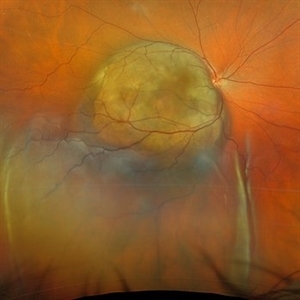

Choroidal Melanoma with Serous Retinal Detachment

Dec 20 2024 by Daniel Davis, OCT-C

67 year old male presenting with large pigmented choroidal mass with serous retinal detachment.

Photographer: Daniel Davis, OCT-C, The Retina Institute

Imaging device: Optos California

Condition/keywords: Retina detachment